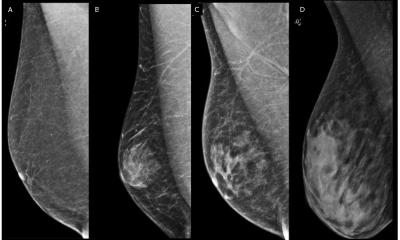

Breast imaging for male and transgender patients: bridging the knowledge gap

Transgender patients face multiple barriers Mammography in cranio-caudal (A) and medio-lateral oblique (B) views in a 52-year-old transgender woman after 5 years of hormone therapy. Anna D’Angelo from the Catholic University of the Sacred Heart in Rome addressed transgender breast imaging, emphasising the importance of correct terminology. Transgender, she clarified, is an umbrella term for read more